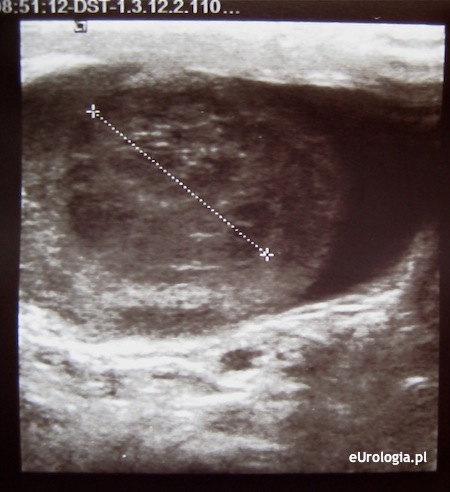

Mam powiększone jądro po lewej stronie. W badaniu USG wyszło, że w dolnym biegunie jądra jest niejednorodny obszar średnicy 20 mm z patologicznym unaczynieniem. Czy na podstawie badania USG wiadomo już, że mam raka jądra? Czy przy prawidłowych markerach można mieć raka jądra?

Rozpoznanie raka jądra stawiane jest na podstawie wyniku histopatologicznego preparatu z orchidektomii czyli po usunięciu jądra. Nieprawidłowy obraz ultrasonograficzny jądra może nasuwać podejrzenie raka. Konieczna jest pilna konsultacja urologiczna. Więcej informacji można znaleźć w dziale: Rak jądra - diagnostyka.

Fot. Nasieniak jądra - obraz USG